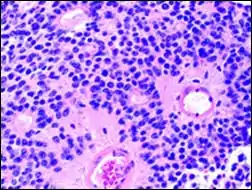

Pineocytomatous/neurocytic pseudorosettes

Histologic features of these two tumors are virtually identical, including their tendency to form neuropilrich rosettes, referred to as pineocytomatous/neurocytic rosettes in central neurocytoma. Both are quite similar to the Homer Wright rosette, but they are generally larger and more irregular in contour. The cells of the pineocytomatous/neurocytic rosettes are also considered to be much more differentiated than the cells forming Homer Wright rosettes in that the nuclei are slightly larger, more rounded, much less mitotically active, and paler or less hyperchromatic. In rare cases, these rosettes may aggregate in a sheet of back-to-back clusters resembling field stone pavement.[2]

Micrograph of pineocytomatous/neurocytic pseudorosettes